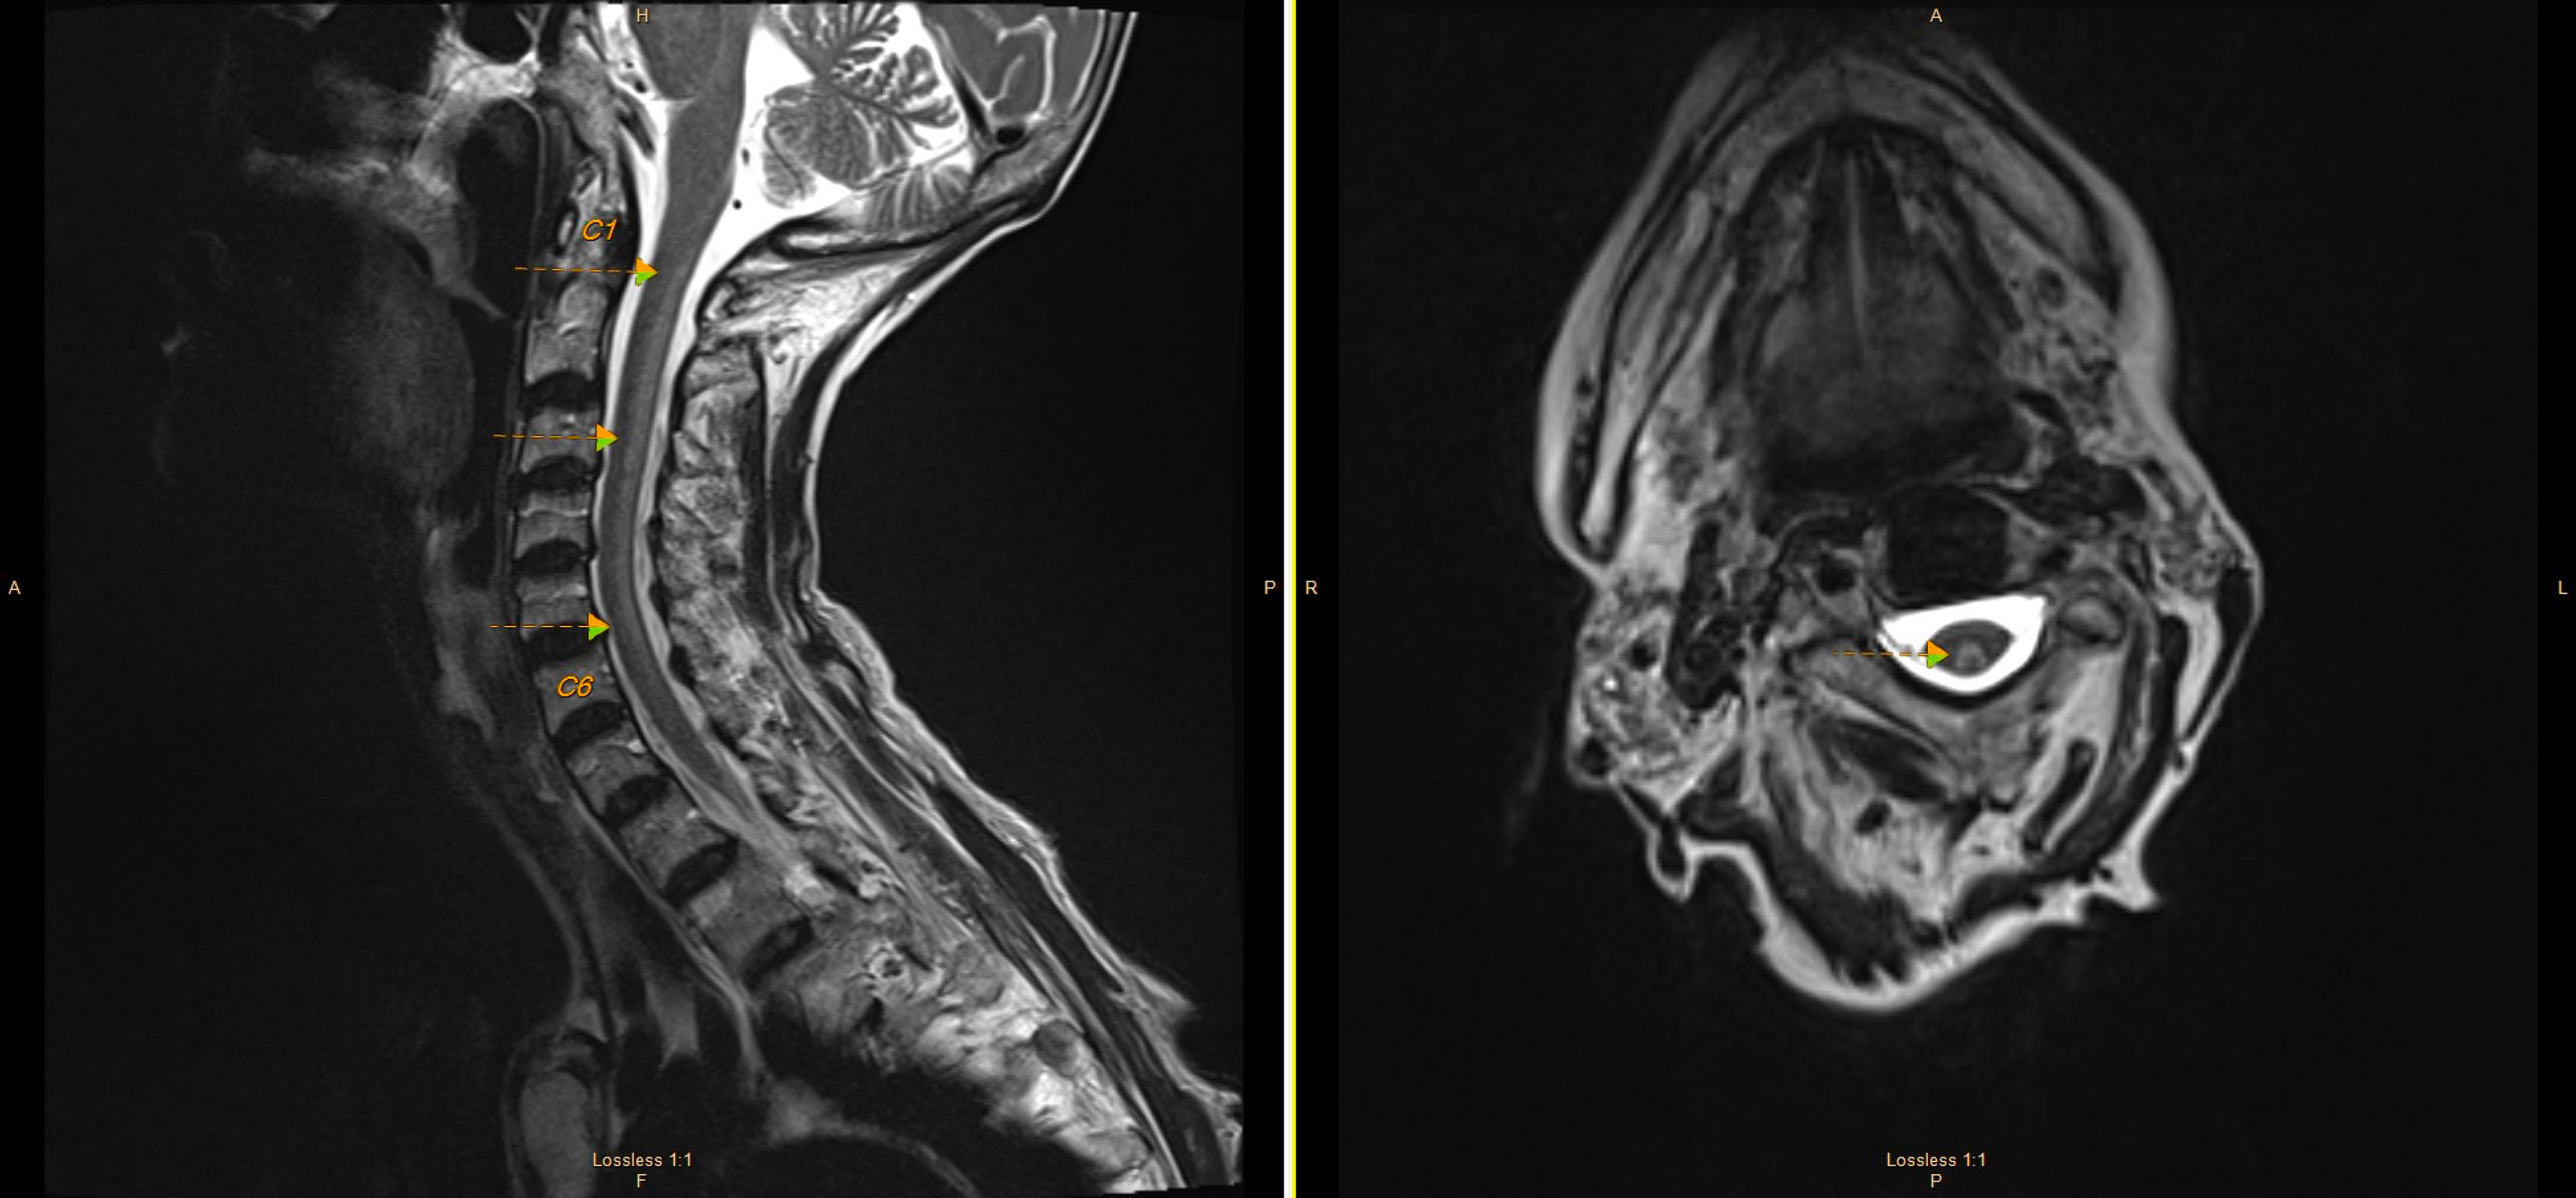

Figure 1 from Copper Deficiency Myeloneuropathy in Autoimmune Disease Copper Deficiency Myeloneuropathy Other rare manifestations include iron overload and/or cirrhosis, which has been described in five patients with copper deficiency. Copper deficiency myelopathy (cdm) was only described within the last decade, and represents a treatable Recently, copper deficiency has become a more recognized cause of myeloneuropathy. Learn about the neurologic manifestations of acquired copper deficiency, a rare condition that causes myelopathy in.. Copper Deficiency Myeloneuropathy.

Figure 1 from Copper Deficiency Myelopathy After Upper Gastrointestinal Copper Deficiency Myeloneuropathy Acquired copper deficiency has been recognised as a rare cause of anaemia and neutropenia for over half a century. Acquired copper deficiency is rare but often seen among patients with intestinal malabsorption syndromes. Other rare manifestations include iron overload and/or cirrhosis, which has been described in five patients with copper deficiency. Learn about the neurologic manifestations of acquired copper deficiency,. Copper Deficiency Myeloneuropathy.

(PDF) Myeloneuropathy due to copper deficiency Clinical and MRI Copper Deficiency Myeloneuropathy Acquired copper deficiency has been recognised as a rare cause of anaemia and neutropenia for over half a century. Copper deficiency myeloneuropathy may have a subacute onset, presenting with a spastic gait and prominent sensory ataxia due. Learn about the neurologic manifestations of acquired copper deficiency, a rare condition that causes myelopathy in. Acquired copper deficiency is rare but often. Copper Deficiency Myeloneuropathy.